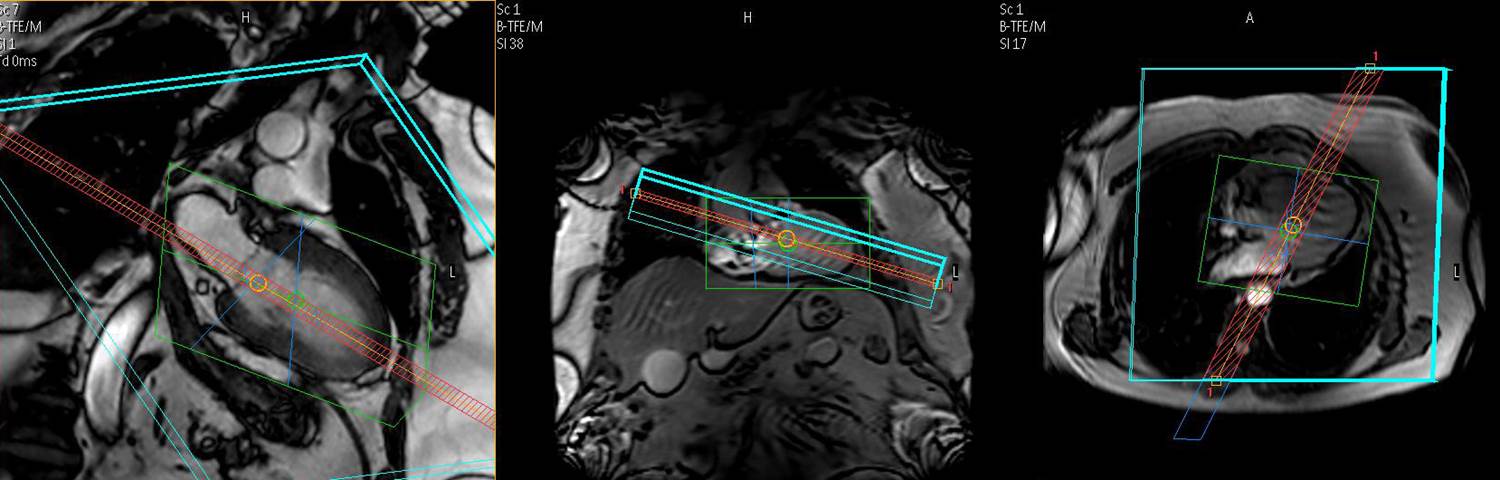

Dieser Komplett-Kurs lehrt nicht nur die Grundlagen der CMR, er befähigt durch weiterführende Studien und spezielles Training unabhängig und selbständig standardisierte CMR-Untersuchungen durchzuführen.

Befundung von mehr als 250 CMR-Untersuchungen, die das gesamte in der Routine vorkommende Spektrum der kardiovaskulären Erkrankungen abdecken. Dies beeinhaltet unter anderem die

- Links- und rechtsventrikuläre Funktion

- Koronararterien-Abbildungen